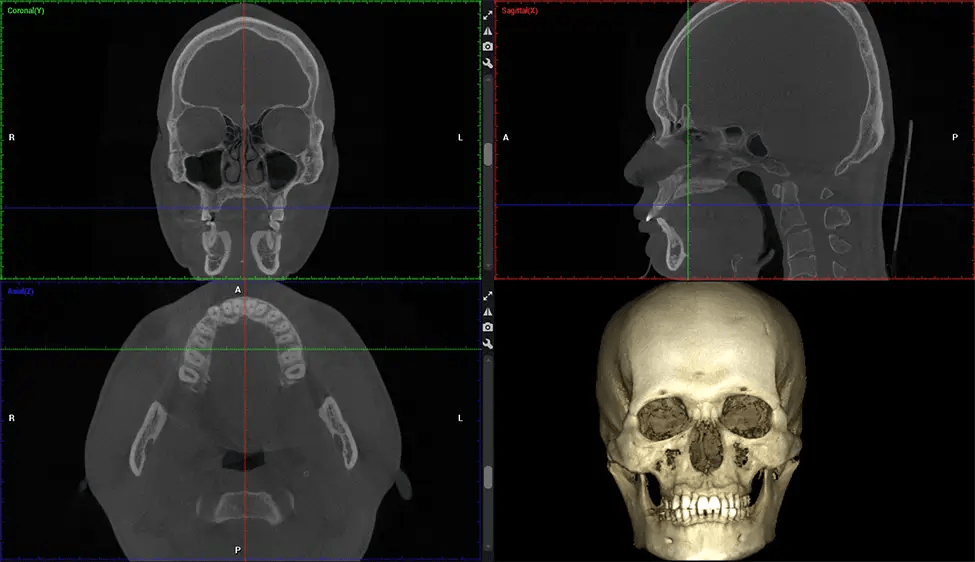

Esta exploración 3D, llamada tomografía computarizada de haz cónico, le brinda a su dentista una imagen más completa de su anatomía bucal y sus procesos patológicos que una radiografía tradicional. A diferencia de las radiografías convencionales, que capturan una imagen 2D de la boca desde varios ángulos, una exploración 3D toma varias radiografías digitales para una imagen. Proporciona una vista completa de la mandíbula, los dientes, los nervios y los tejidos blandos. Esta vista mejorada permite a los dentistas detectar problemas menores que no son visibles en las exploraciones 2D tradicionales, como muelas del juicio impactadas o fracturas óseas en la cavidad sinusal.

Existen muchos beneficios al utilizar la tecnología CBCT, especialmente en comparación con el formato tradicional de rayos X 2D. Una de las ventajas más importantes de las exploraciones CBCT es que proporcionan mucha más información que las radiografías tradicionales. Una exploración le permite a su dentista ver imágenes desde todos los ángulos de su mandíbula y boca, incluidos los senos nasales, la cavidad nasal, los pómulos y otras áreas circundantes. Esta información adicional ayuda a su dentista a elaborar un plan de tratamiento integral que aborde todos los aspectos de su salud bucal.

Planmeca Viso G7 CBCT (Cone Beam CT Scan) está diseñado para superar las demandas de los líderes de la industria, los especialistas y las grandes instituciones. Tiene un gran sensor de ø25×30 cm con cuatro cámaras integradas. Puede capturar tamaños de volumen ilimitados, desde ø3×3 cm hasta ø30x30cm, capturando el casquete escutelario a través de C7 en la columna cervical. Planmeca Viso G7 ofrece el escaneo de volumen único más grande de la industria de ø30×19 cm. Está preparado para manejar modalidades de imágenes avanzadas como la tecnología Planmeca ProFace® y Planmeca 4D™ Jaw Motion. El soporte occipital para la cabeza permite una visión sin obstáculos del tejido facial.

Planmeca es el único fabricante clínicamente probado que reduce drásticamente la radiación del paciente sin sacrificar la calidad de la imagen. Planmeca Ultra Low Dose™ logra una reducción promedio de la dosis del 77% sin una reducción estadística en la calidad de la imagen, lo que permite a los médicos incorporar imágenes 3D en protocolos de rutina con una radiación efectiva al paciente a menudo inferior a la de las imágenes intraorales 2D.. Esto aumenta la atención al paciente, permite a los médicos diagnosticar más odontología y, a menudo, antes en la progresión de la enfermedad, que con imágenes 2D solas.

Las unidades Planmeca 3D también incluyen la única tecnología de corrección y detección de movimiento del paciente de la industria, Planmeca CALM™. Esta tecnología corrige el movimiento durante la adquisición de CBCT reduciendo el riesgo de repeticiones.